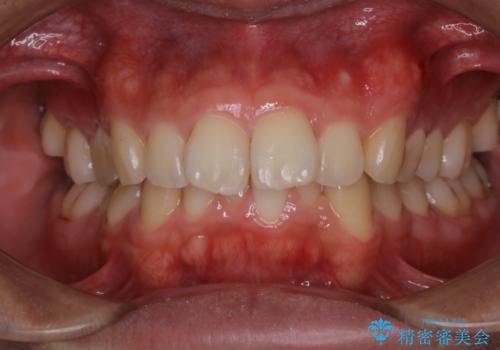

虫歯ではなく、歯の着色

- 歯が黒くて虫歯かもしれないとのことで来院されました。虫歯ではなく、着色が付着してしまっていたためPMTC30分コースできれいに除去しました。

黒や茶色くなっている部分が、着色なのか、虫歯によるものなのかは判別が難しいことがあります。そのため、定期的にPMTCを行うことで状態の確認が的確に行えます。

PMTCとは、専門的な機械や材料を使用したしっかりとしたクリーニングです。

治療が開始される前などにも、全体的にクリーニングを行いご自身本来の歯の色、状態を精密に確認することが大切です。